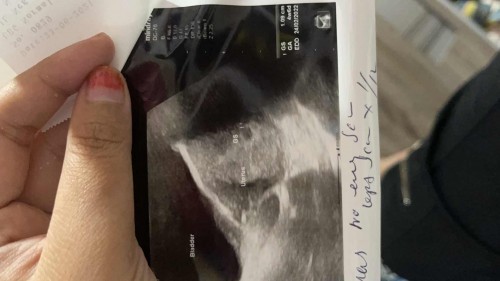

salam dan hi, kalau ikutkn LMP sy, skrg sy hamil 7minggu 4hr. tapi tadi sy pergi scan, doktor bgtau sy br 4minggu 6hri. ada ke ibu ibu di sini alami perkara yg sama?

VIP Parentssalam dan hi, kalau ikutkn LMP sy, skrg sy hamil 7minggu 4hr. tapi tadi sy pergi scan, doktor bgtau sy br 4minggu 6hri. ada ke ibu ibu di sini alami perkara yg sama?